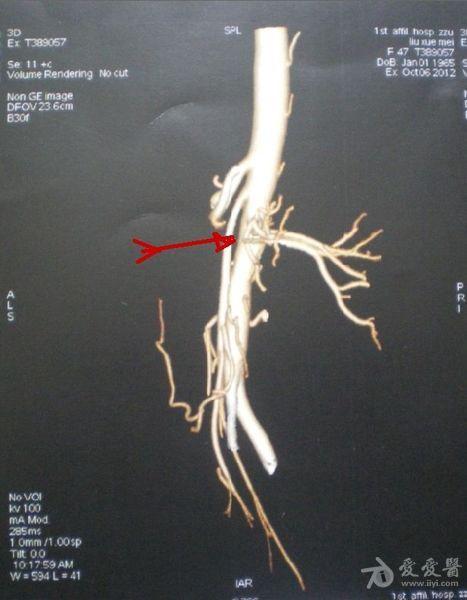

肠系膜上动脉压迫综合征良性十二指肠瘀滞症

肠系膜上动脉压迫综合征(良性十二指肠瘀滞症)